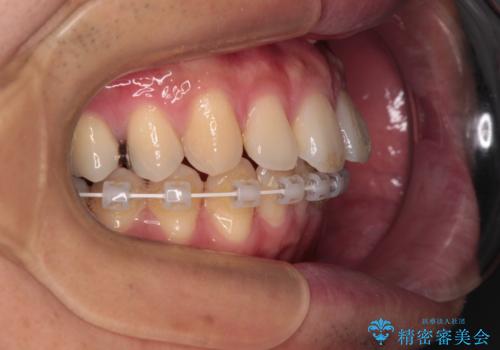

- 矯正装置

- ハーフリンガル

インビザラインは自己管理が煩わしく、表側のワイヤー装置は目立つので避けたいとのことで、上顎だけが裏側装置のハーフリンガルにて矯正治療を行うこととしました。

矯正治療中に結婚式があったそうですが、隙間も改善しており、一部装置を外すことなく挙式できたとのことでした。